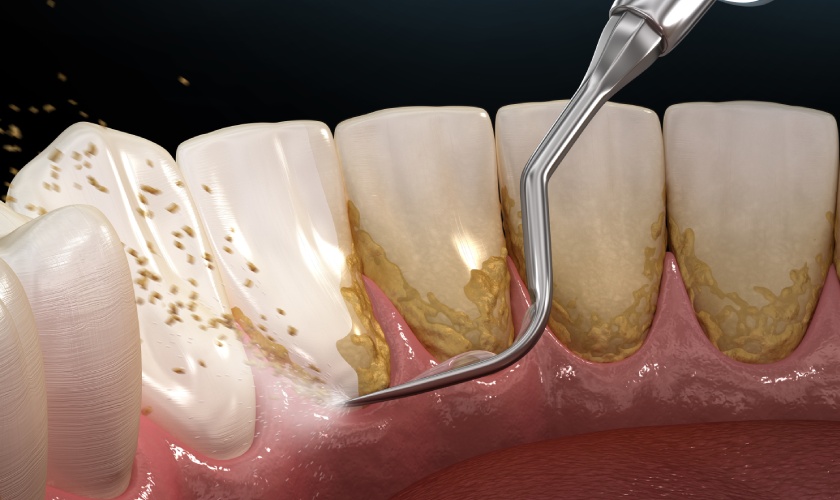

Bên cạnh đó, Bác sĩ ứng dụng công nghệ cạo vôi răng bằng sóng siêu âm hiện đại, khắc phục những nhược điểm của bộ dụng cụ lấy vôi răng thủ công. Nhờ đó, vôi răng được loại bỏ nhanh chóng, không gây đau, không chảy máu và không biến chứng.

Công nghệ cạo vôi răng bằng sóng siêu âm nhẹ nhàng loại bỏ vôi răng